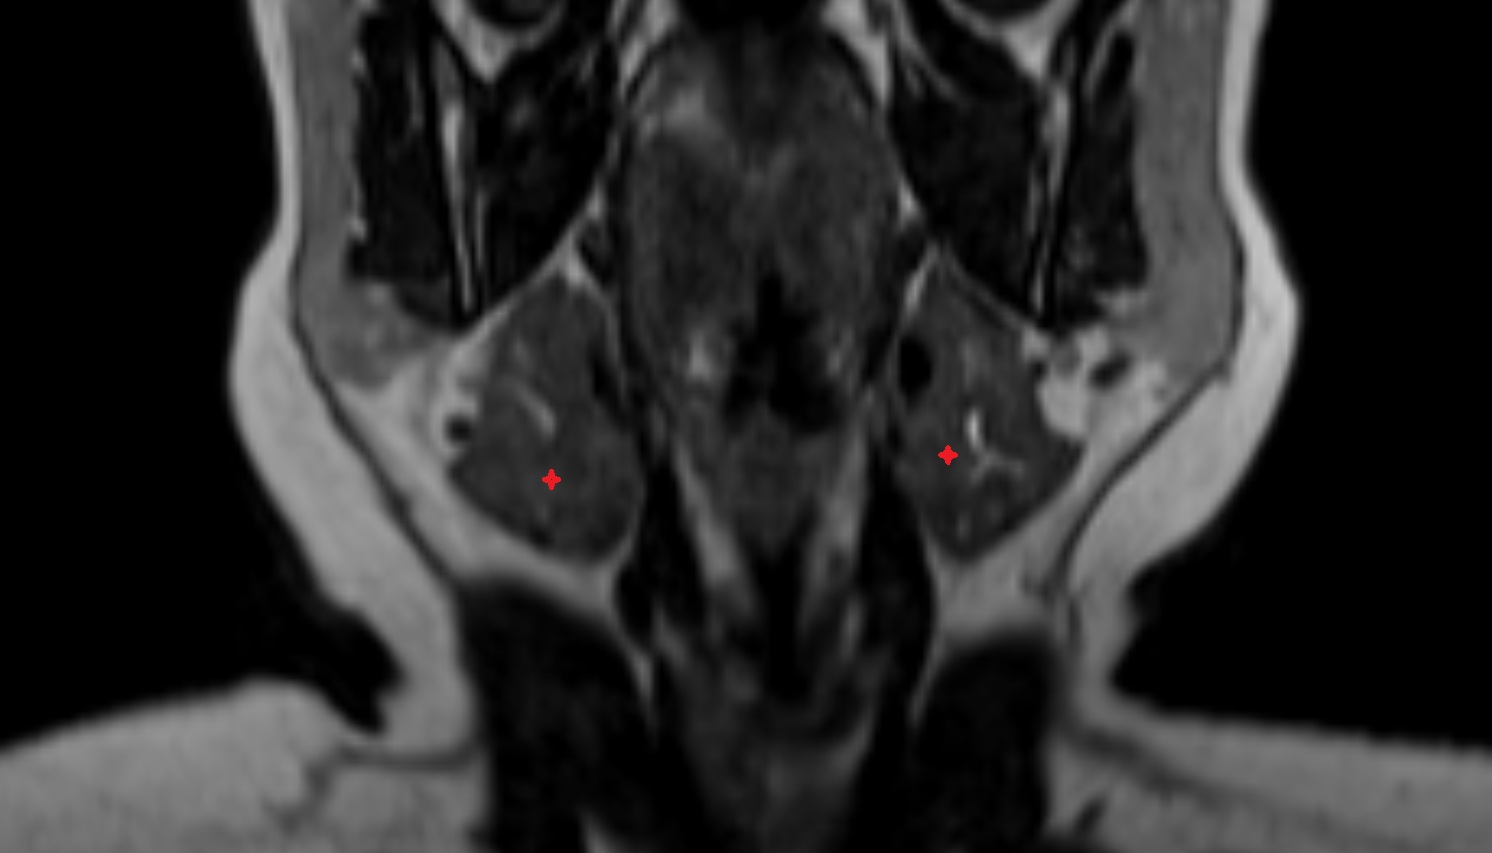

- Medial pterygoid muscle